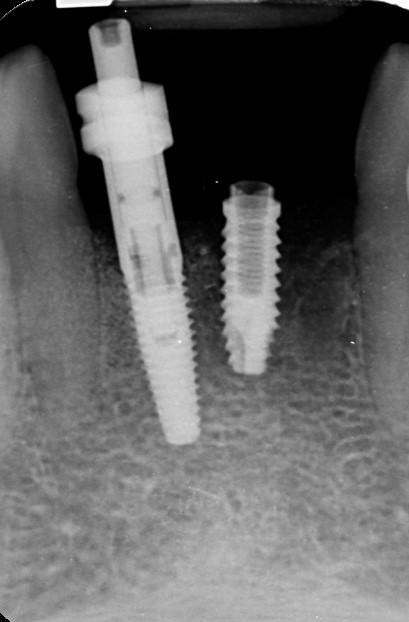

Les agradecería me suministrarán información acerca de marca, modelo y plataforma del implante que no tiene conectado un coping. Es un hexágono externo, la altura del hexágono es mayor que la del hexágono externo de Branemark System. La métrica del implante no es compatible con el tornillo que atornilla el coping de cubeta abierta de los implantes Branemark System de la casa Nobel Biocare,  tanto para NP como para RP. La métrica si es compatible con la del tornillo del coping de cubeta abierta del implante hexágono externo de Klockner SK-2.

Es un paciente referido para proceder a su rehabilitación, el implante es superviviente , lleva varios años de uso, ha perdido hueso, y el hexágono externo tiene defectos, producidos probablemente por una fresa, ya que hace algún tiempo  tuvieron que retirar la corona antigua cortándola.  El implante vecino es un Replace Select NP. Muchas gracias.

Es un implante Phibo TSH S2, que tiene un hexágono diferente. Puedes contactar con ellos directamente.